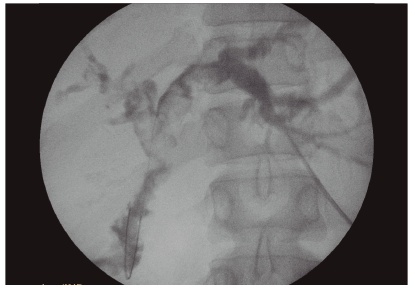

Se decide realizar el drenaje biliar de forma inmediata, teniendo en cuenta que se trataba de una paciente con colangitis severa. Debido al antecedente quirúrgico se optó por un acceso percutáneo. Se colocó por vía transhepática un drenaje interno-externo y se realizó una colangiografía donde se evidenciaron múltiples litos en ambas ramas hepáticas principales y en sus ramas secundarias. Asociado a esto, se observaba una estenosis de la hepático-yeyuno anastomosis (Figuras 1 y 2).